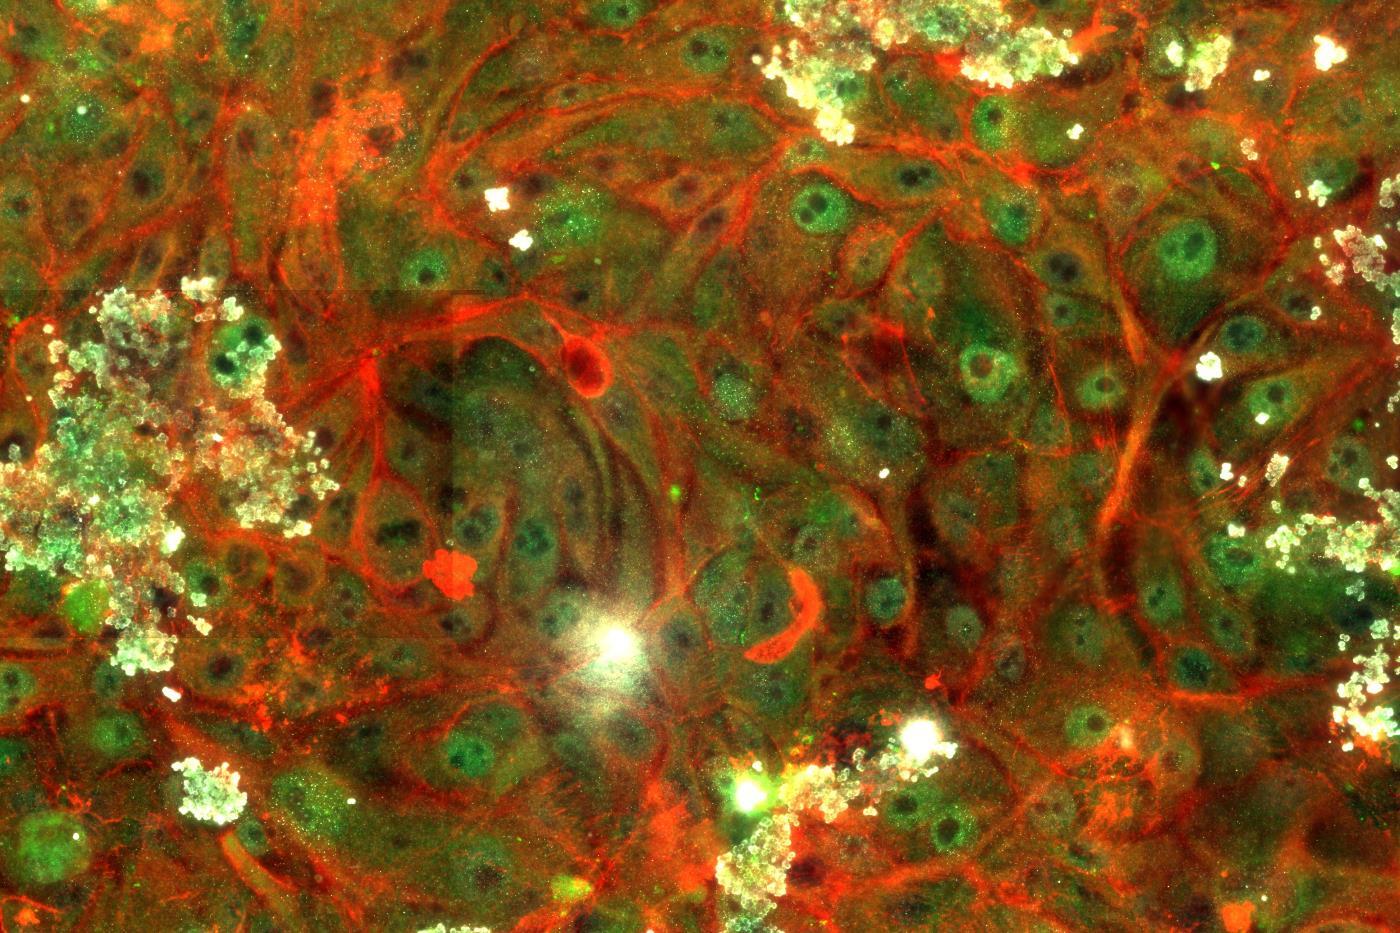

“Ear”

Robert Tombes, Ph.D., professor, Department of Biology, College of Humanities and Sciences

“Ear” shows muscle fibers (in green) and tubulin (in red), portraying the “axonal innervation of the ear into sensory structures.” According to the exhibit’s display, the image “suggests novel ways to regrow auditory sensors within the inner ear.”